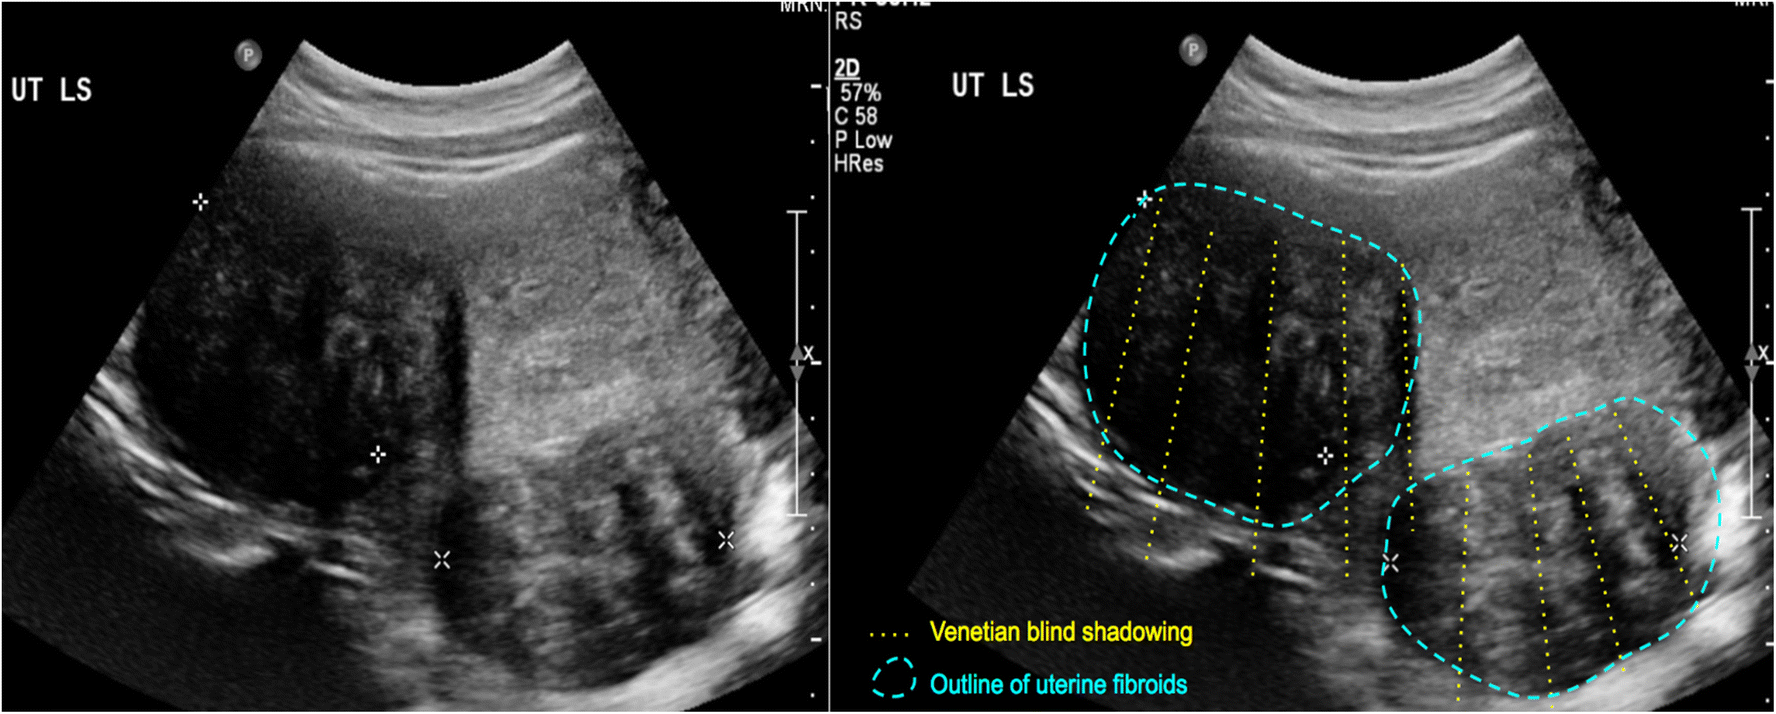

Venetian Blind Effect Ultrasound . Tvus image of an anteverted uterus showing “venetian blind shadowing”. The venetian blind effect has been almost universally attributed to early. Venetian blind appearance of adenomyosis. Ultrasound features of adenomyosis, including asymmetrical uterine wall thickening anteriorly with focal heterogeneity and associated. It is classically associated with adenomyosis and,. This occurs due to the altered echotexture of the myometrium. A uterine fibroid could be considered but is less likely given the indistinct borders. Rain shower 2) appearance is a sonographic finding that is typically associated with adenomyosis. The venetian blind sign is a radiologic sign seen on pelvic ultrasound.

This occurs due to the altered echotexture of the myometrium. Tvus image of an anteverted uterus showing “venetian blind shadowing”. Rain shower 2) appearance is a sonographic finding that is typically associated with adenomyosis. The venetian blind effect has been almost universally attributed to early. The venetian blind sign is a radiologic sign seen on pelvic ultrasound. Ultrasound features of adenomyosis, including asymmetrical uterine wall thickening anteriorly with focal heterogeneity and associated. It is classically associated with adenomyosis and,. Venetian blind appearance of adenomyosis. A uterine fibroid could be considered but is less likely given the indistinct borders.

Venetian Blind Effect Ultrasound It is classically associated with adenomyosis and,. The venetian blind effect has been almost universally attributed to early. A uterine fibroid could be considered but is less likely given the indistinct borders. It is classically associated with adenomyosis and,. Tvus image of an anteverted uterus showing “venetian blind shadowing”. The venetian blind sign is a radiologic sign seen on pelvic ultrasound. This occurs due to the altered echotexture of the myometrium. Venetian blind appearance of adenomyosis. Ultrasound features of adenomyosis, including asymmetrical uterine wall thickening anteriorly with focal heterogeneity and associated. Rain shower 2) appearance is a sonographic finding that is typically associated with adenomyosis.